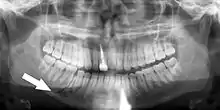

Panoramic radiographs have the capability to demonstrate a portion of the neck and display atheromas (calcifications in the carotid artery) which are an indication of both local and generalized (systemic) atherosclerosis. Atherosclerosis of the coronary arteries leading to myocardial infarction (heart attack), and atherosclerosis of the carotid artery leading to stroke are the number one and number three most common causes of death in the United States.[6]

There is interest to look at panoramic radiographs as a screening tool, however further data is needed with regards if it is able to make a meaningful difference in outcomes.[7]